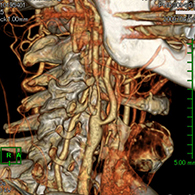

脳梗塞の原因となる頚動脈狭窄症に対して内膜剥離術を行う

56歳男性、左半身麻痺で発症した。

<術前画像所見>

右側で頸部内頚動脈が細くなっているため右脳に脳梗塞を生じた。

<術後画像所見>

頸部狭窄は解消しており、新たな脳梗塞など生じていない。